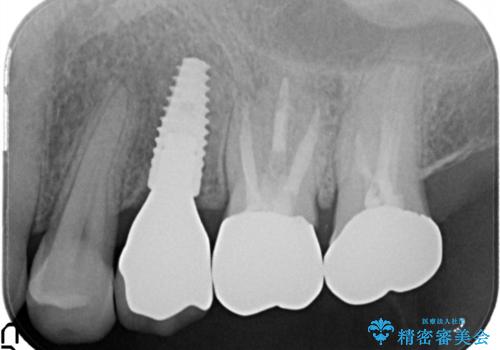

歯周病の進行した歯の抜歯。オールセラミッククラウン

- 以前に他院にて治療した歯が痛いことを主訴に来院されました。

最後方臼歯は根尖部まで歯周病が進行しており、抜歯を行なったのち、残存歯は歯周外科を行なったのちオールセラミッククラウンにて修復治療を行なっています。